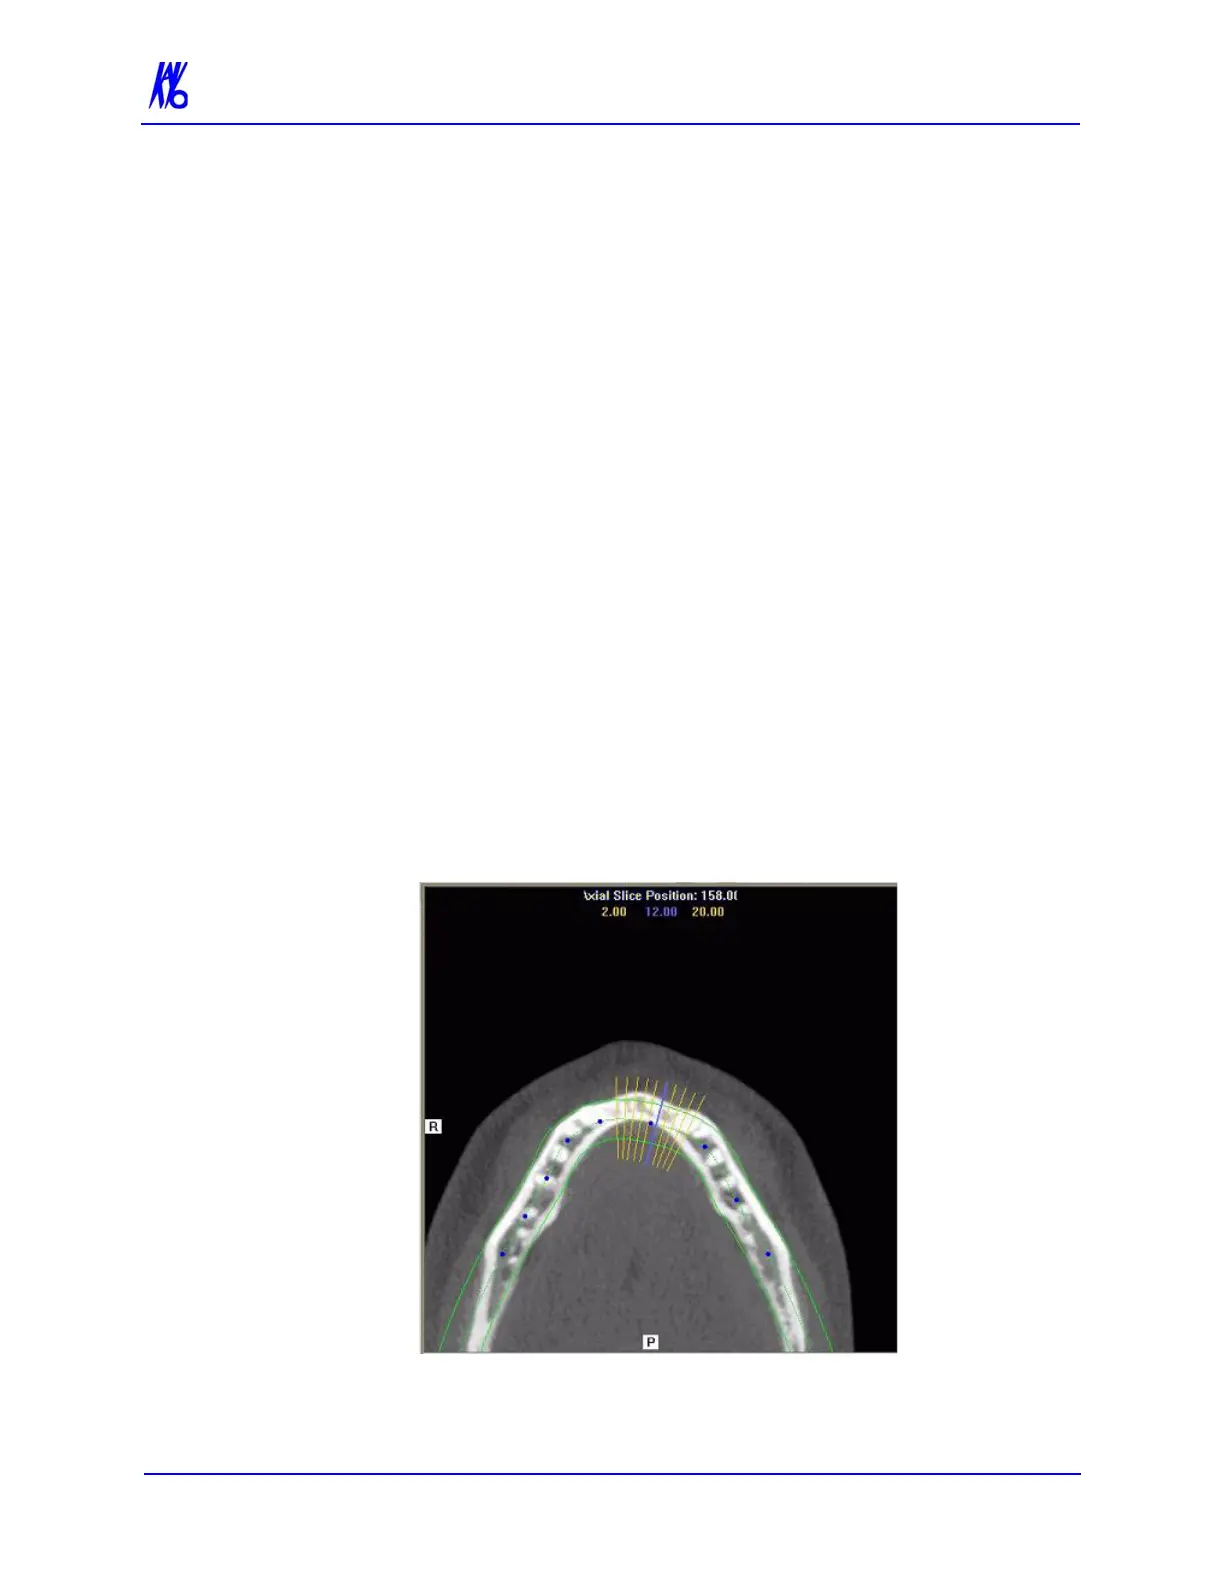

axial slice position view) and modify the criteria used to

generate the axial views (lower right).

Cross Section Views (lower right) shows cross section

details of the anatomy of interest as specified on the axial

slice position view and the panoramic map view. The mouse

scroll wheel is active to scroll through the slices.

Patient position indicators are used on the Implant Planning Screen

to indicate the orientation of the displayed data. These are:

R = Right Side

P = Posterior

B = Buccal

1. Click and drag the blue dots on the axial slice position view to

adjust the image displayed on the panoramic map view.